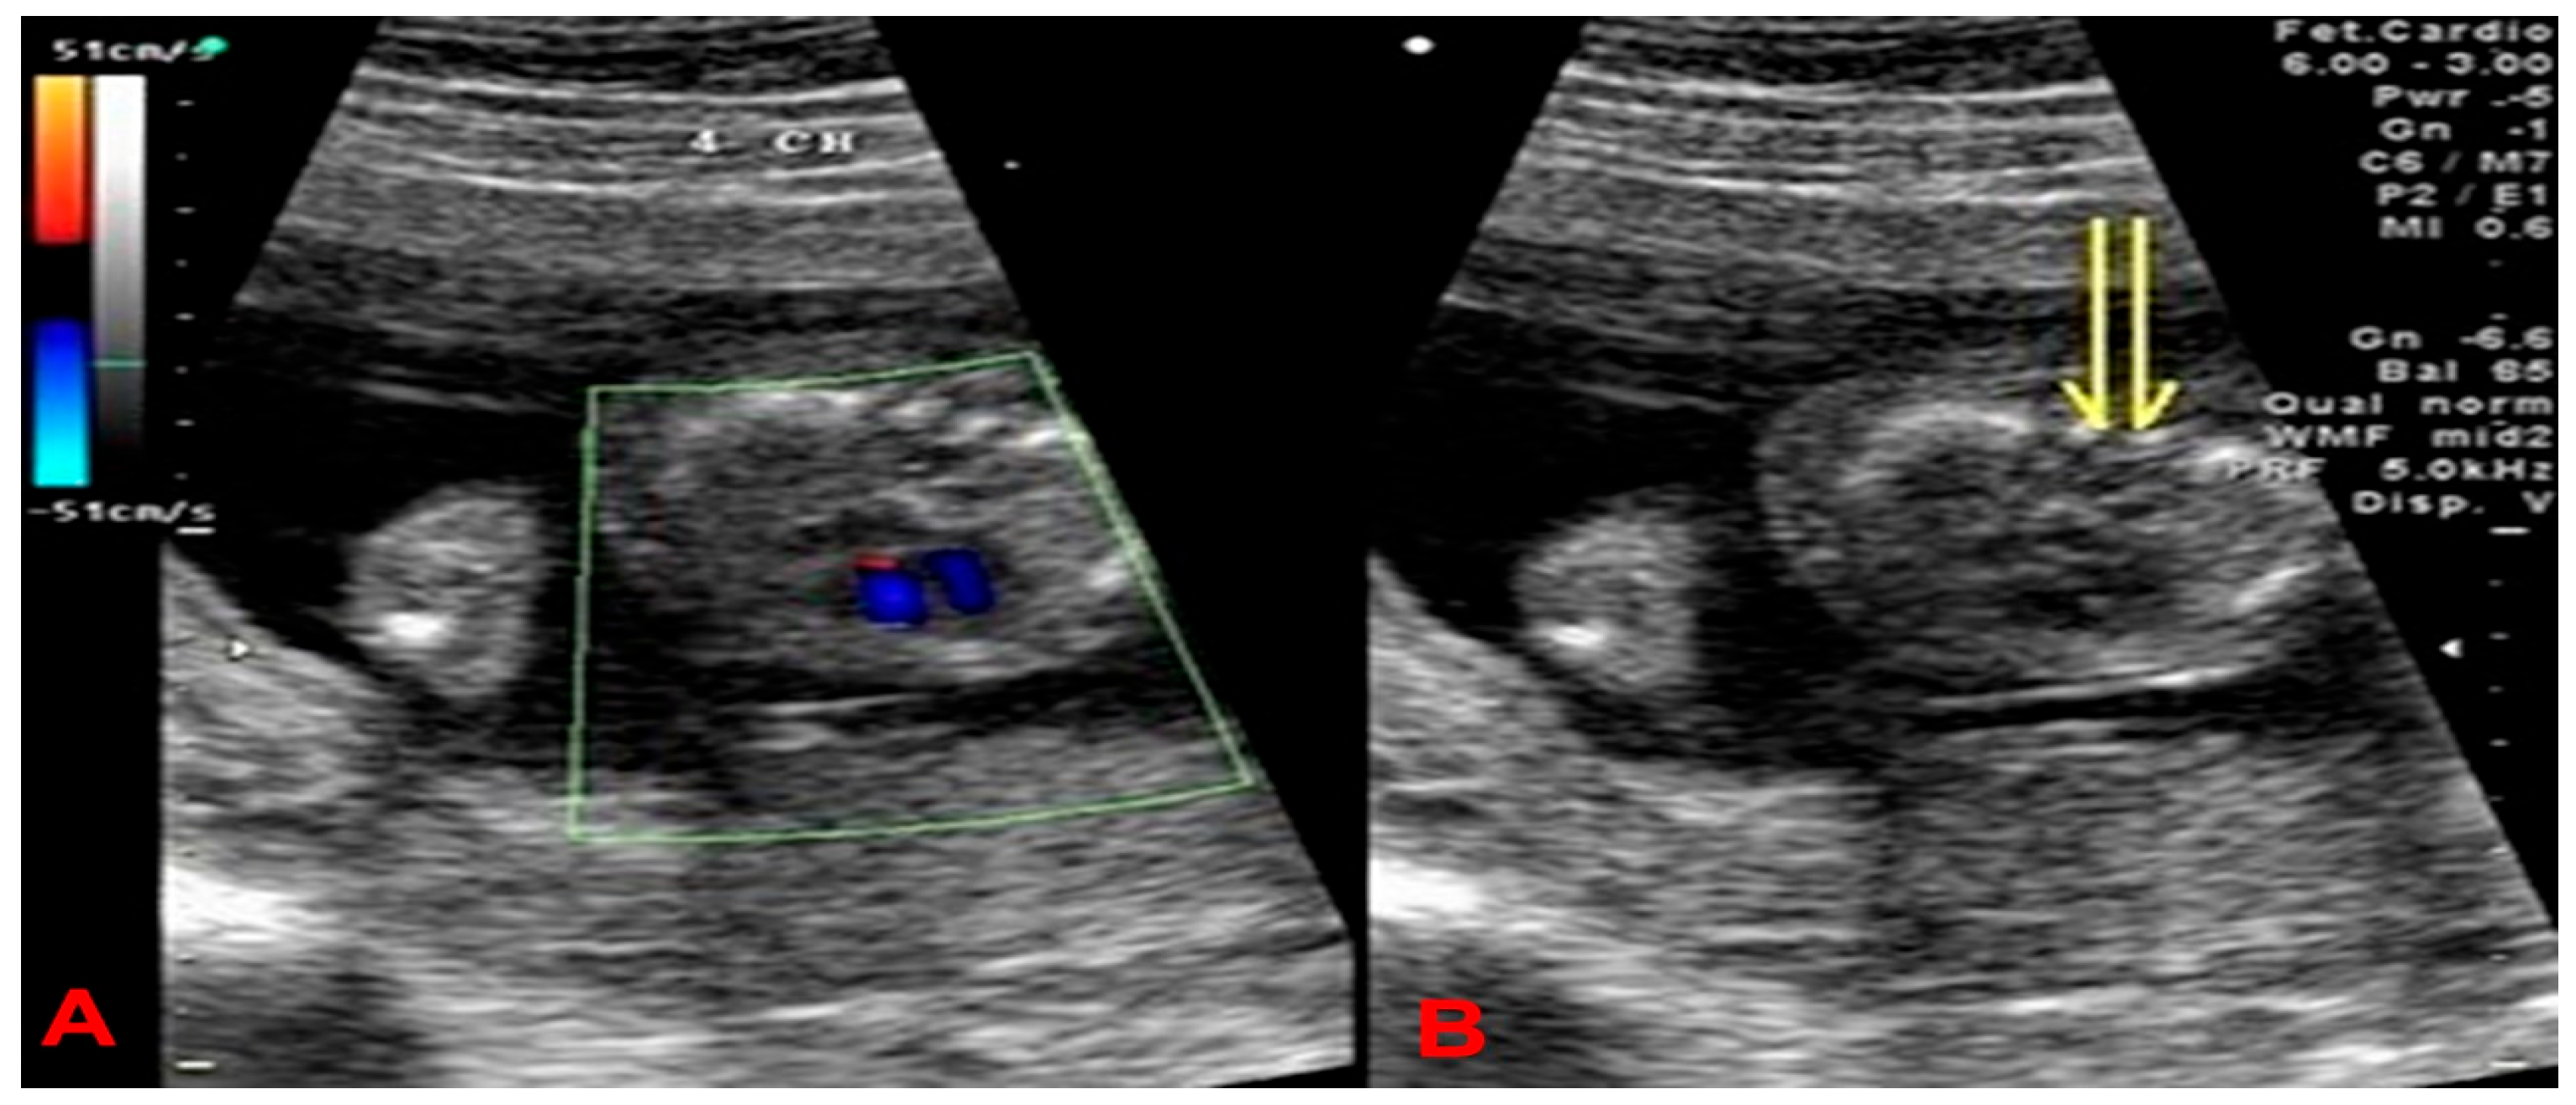

2. Case Presentation